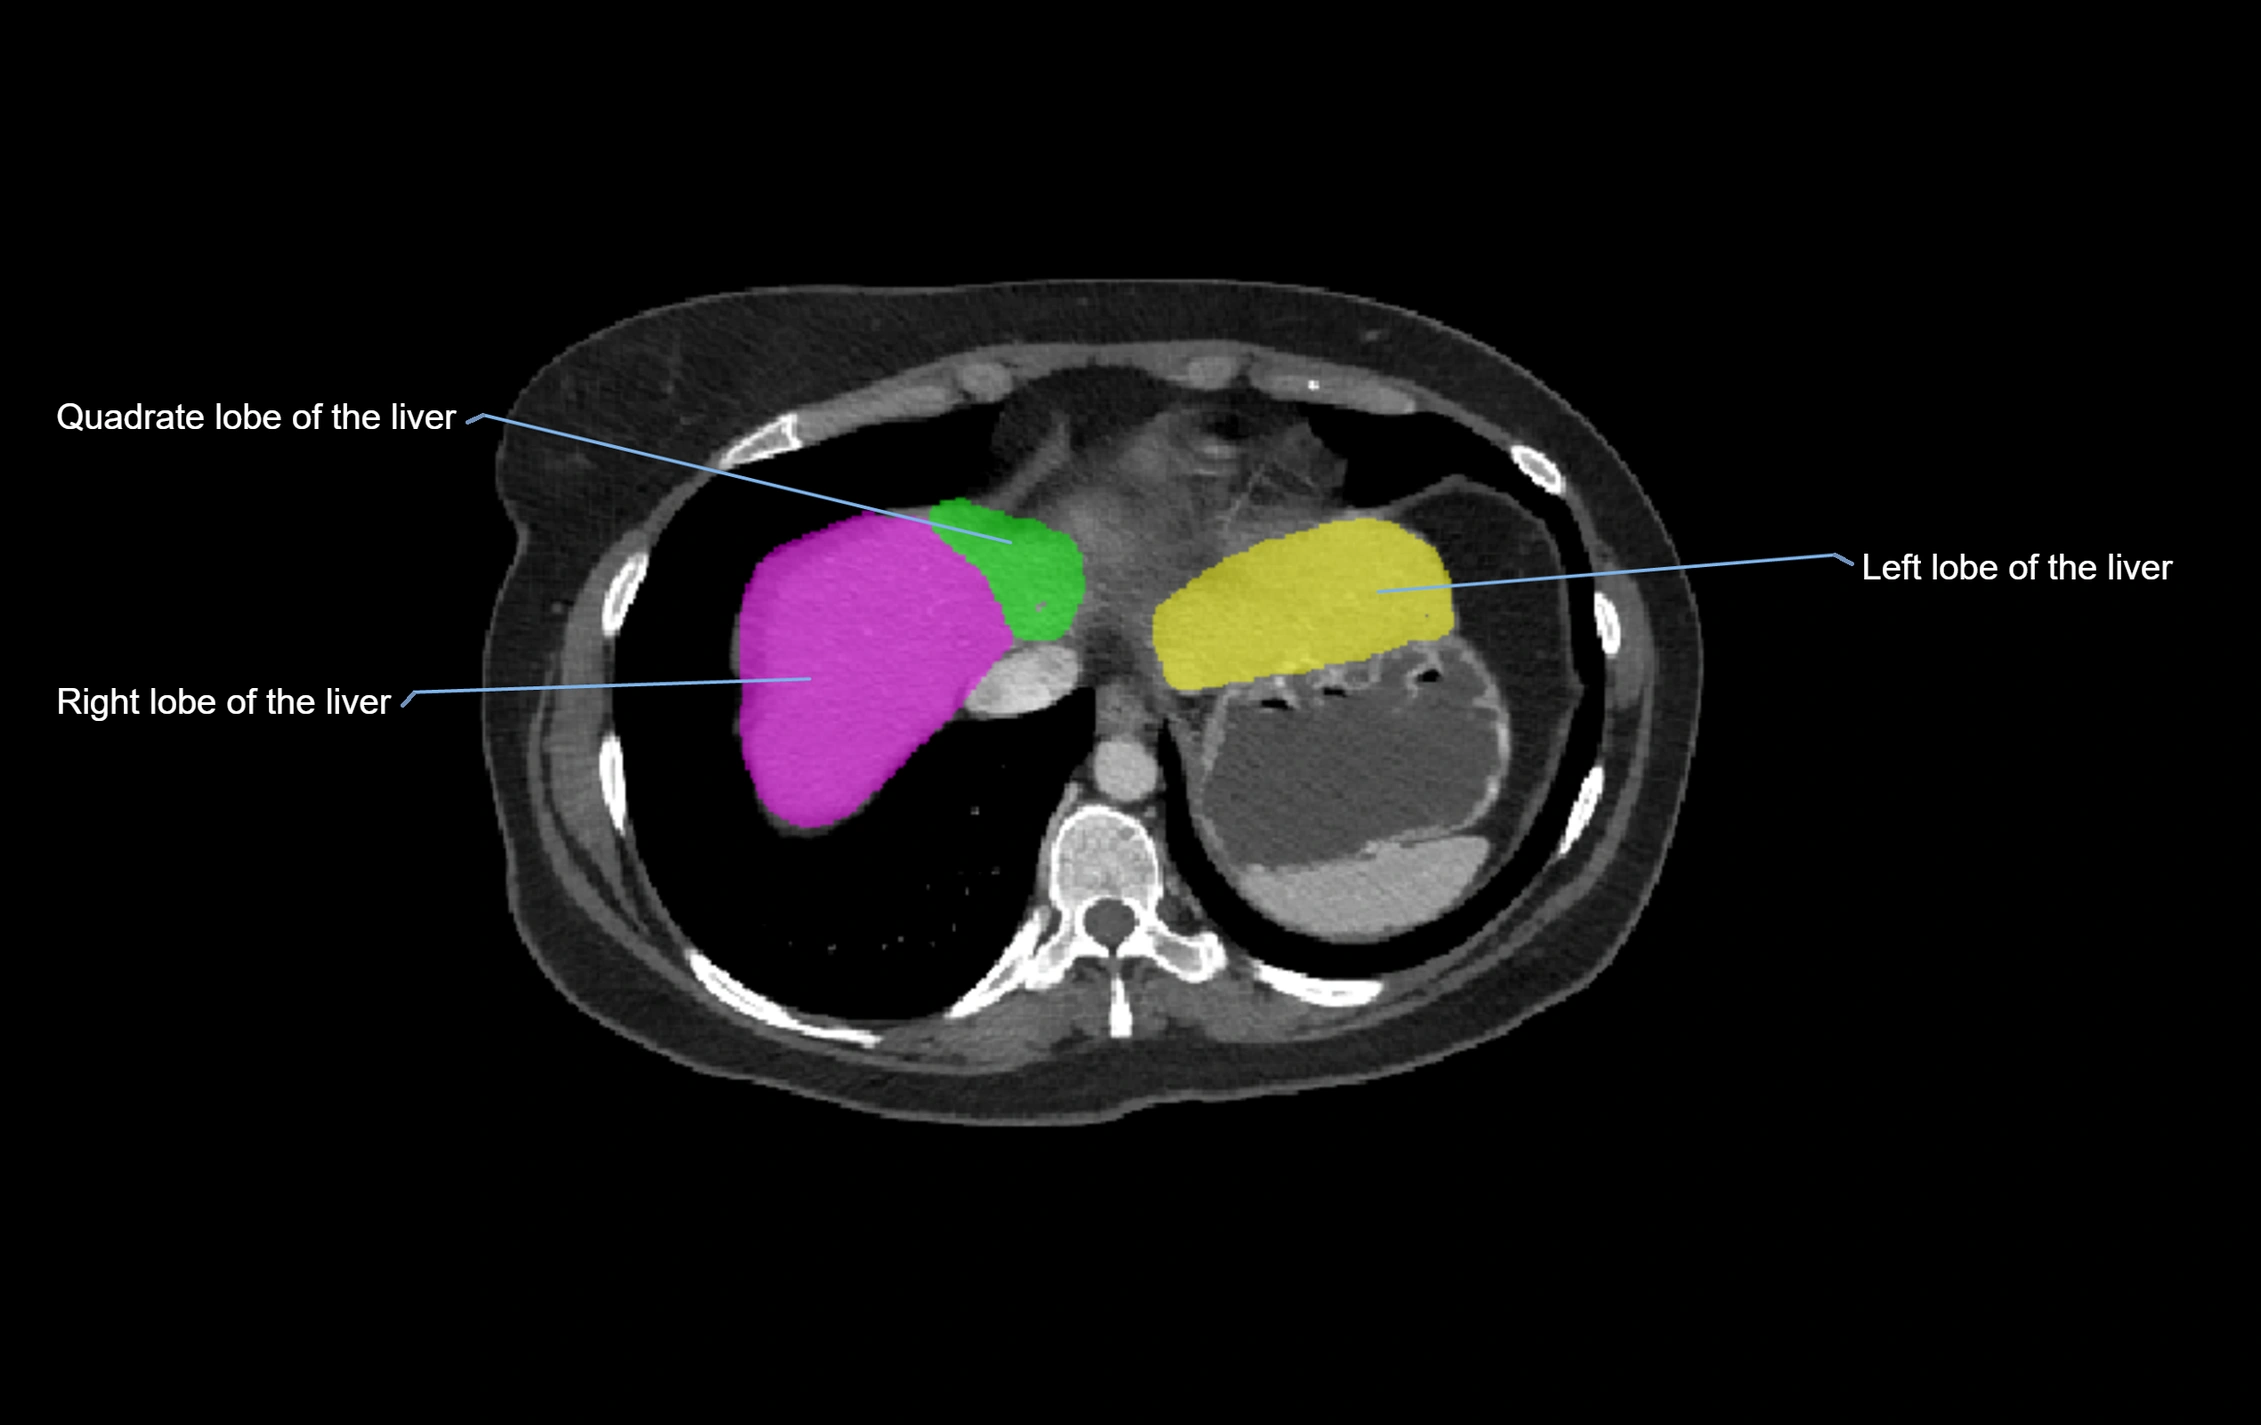

CT Image

image